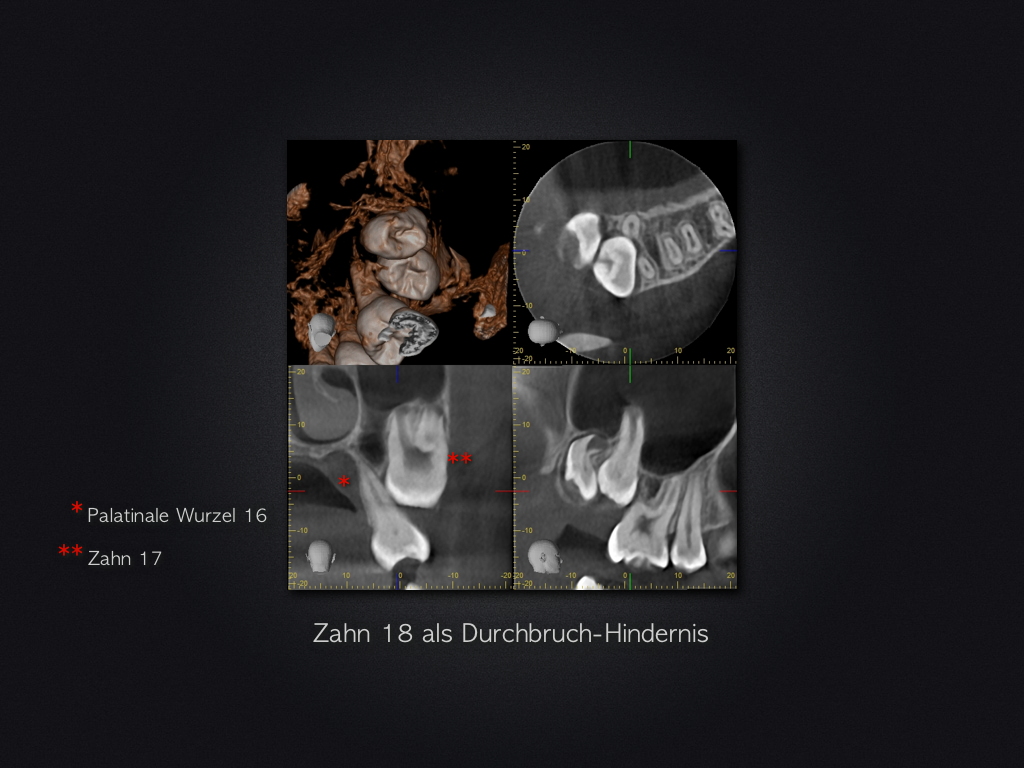

2D vs. 3D (XXIII)